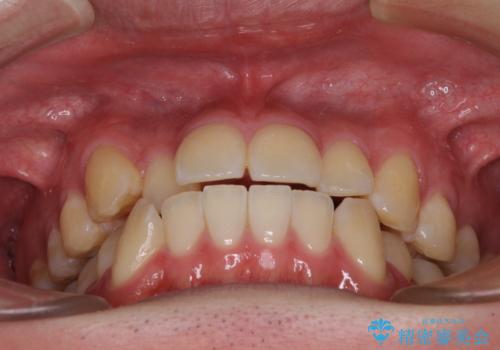

八重歯と前歯のクロスバイト ワイヤー装置で短期間矯正

- 八重歯を気にして来院された患者様です。

上顎側切歯(前から2番目の歯)が内側に転位している歯列は、インビザラインでは排列が困難であることが多いため、期間を短く、より良い仕上がりとするため、ワイヤー装置にて矯正治療を行うこととしました。